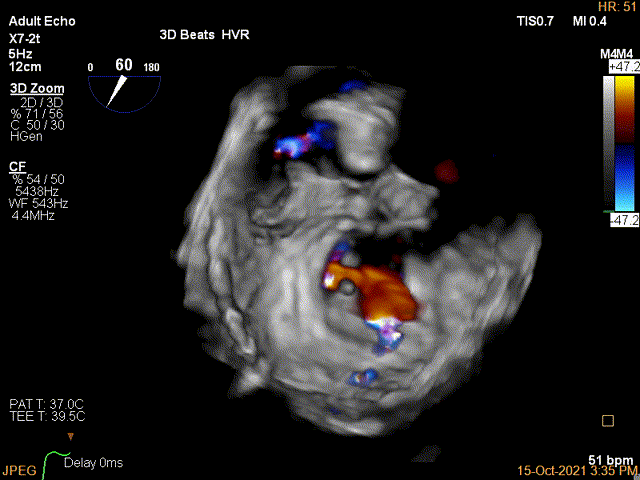

3D-color证实残余分流主要位于内侧2区

第一个夹子放置后二尖瓣口平均跨瓣压差:4mmHg

Color第二个夹子内侧残余小束分流,宽2.3mm

第二个夹子放置后二尖瓣口平均跨瓣压差:4mmHg